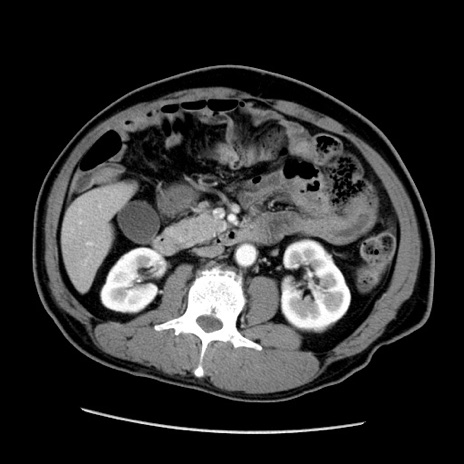

症例22(横断像)

【症例】50歳代男性

【主訴】腹痛

【現病歴】AVMからの被殻出血のため回復期リハ病棟入院中。 本日午後3時頃急に下腹部痛が出現した。

【既往歴】AVM、被殻出血、虫垂炎、高血圧

【身体所見】意識晴明、左半身不全麻痺、会話の理解は良好、36.5°C、腹部:膨隆、全体に板状硬、下腹部正中に圧痛点あり、反跳痛-、筋性防御不明、右下腹部にope scar

【データ】WBC 9400、CRP 0.06